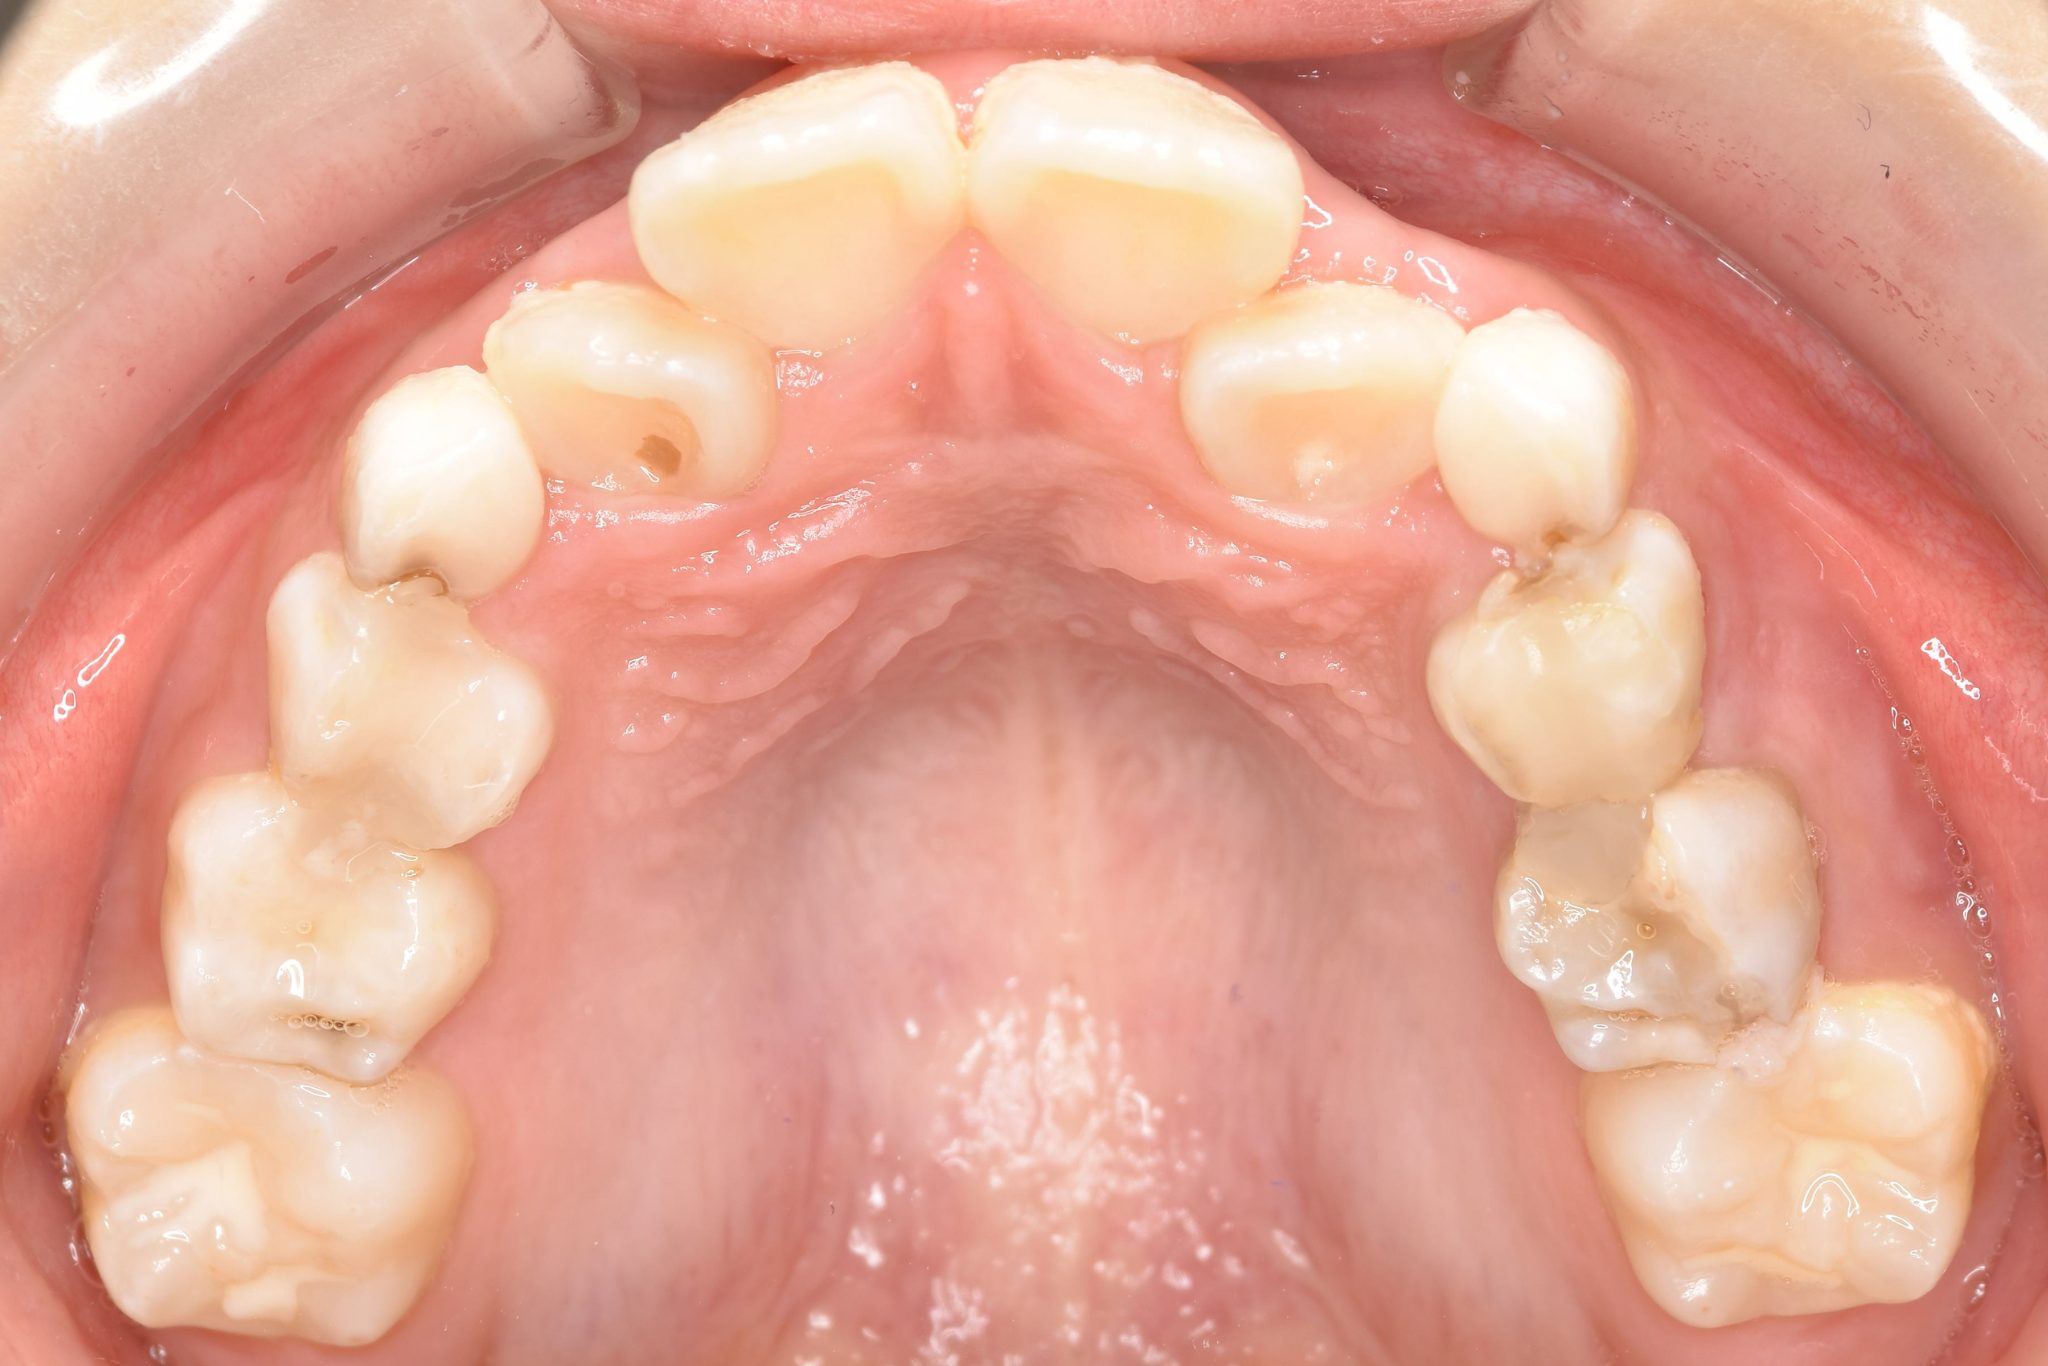

全顎ワイヤー矯正 症例_185

主訴 歯並び|横から生えている大人の歯

施術内容 小児矯正1期治療

治癒期間 4年間

費用 522,960円(税込)

リスク・副作用 違和感、不快感、痛み